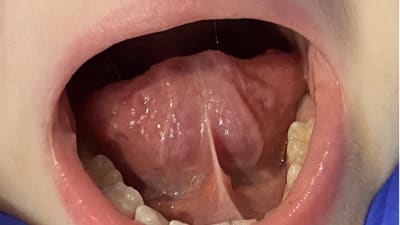

Online Only Online Only Tongue Restriction Questionnaire: A New Screening Tool to Identify Tongue-Tied Patients By Nicholas R. Rendell, PhD, Richard Baxter, DMD March 01, 2021 21 min read